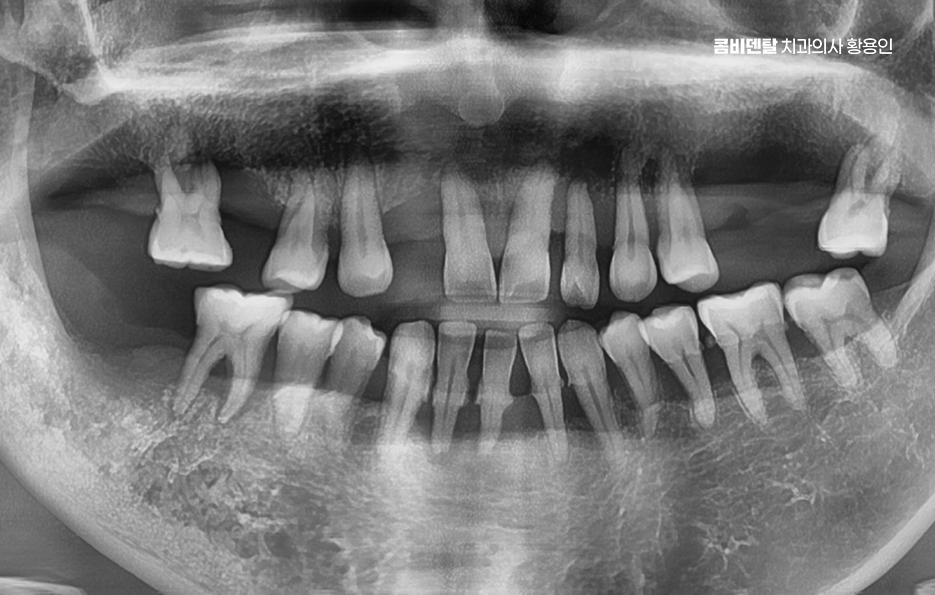

출처 아카이브 열기예전부터 치아가 썩는 속도가 남들보다 빠르다는 이야기를 자주 들었어요, 어릴 때는 단순히 양치질을 대충 해서 그런 줄 알았고, 조금 지나선 타고난 체질이라며 스스로를 위로했지만, 시간이 지나면서 그게 그냥 습관이나 체질의 문제가 아니라 오랜 시간 방치한 결과였다는 걸 뒤늦게 알게 됐어요, 직장 다니면서 바쁘다는 핑계로 통증이 있어도 참고, 잇몸이 붓거나 피가 나도 대수롭지 않게 넘기기를 반복했고, 그 결과 어느 날부터 하나둘씩 치아가 흔들리기 시작하더니 결국은 몇 개의 치아를 잃게 되었어요. 처음엔 하나 빠졌을 때도 '뭐 어금니 하나쯤 없다고 당장 큰일 나는 건 아니지' 싶었고, 보이지도 않으니까 신경 안 쓰고 넘겼는데, 그게 큰 착각이었어요, 하나 빠지고 나면 그 옆 치아가 기울기 시작하고, 반대쪽 어금니는 씹는 부담이 늘어나고, 그렇게 전체적인 균형이 무너지기 시작하는데, 그 과정이 생각보다 빨랐어요

이처럼 치아의 상실은 단지 치아 하나를 잃은 문제로 끝나는 것이 아닌 주변 치아 뿐 아니라 저작력, 심미성, 전체 교합 등에도 영향을 연쇄적으로 주기 때문에 씹는 불편함에서 그치는 것이 아날 나아가 전신 건강과 삶의 질까지 영향을 줄 수 있는데요

50대에 접어들면서 치아를 하나씩 군데군데 잃게 되는 경우가 의외로 많으며 어느 날 갑자기 이 하나가 빠지는 게 아니라, 충치로 인해 오래 방치했던 치아가 무너지고, 잇몸이 약해져서 흔들리던 치아가 뽑히고, 그러다 보면 어느새 위아래, 양쪽 어금니, 앞니 사이사이에 비어 있는 자리가 생겨버리는 거예요.

이런 상태를 “부분 무치악”이라고 부르는데 이러한 상태에서 50대임플란트 치료 계획을 세운다는 것은 전체 치열과 기능까지 다시 설계해야 하는 복잡한 치료가 될 수 있어서 50대에 여러 치아를 잃은 경우엔 임플란트 치료 계획이 단순한 ‘치아 대체’ 수준이 아니라, 전체적인 구강 재건이라는 개념으로 접근해야 할 수 있어요

일단 군데군데 치아가 빠진 상태를 방치하면 문제가 걷잡을 수 없이 커질 수 있는데 빈자리를 기준으로 양옆 치아가 쓰러지듯이 기울고, 맞물리는 반대편 치아는 내려오며 그렇게 전체 치열이 무너지게 되고, 나머지 치아들이 계속해서 무리한 힘을 받으면서 결국 건강하던 치아까지 하나둘씩 손상되는 거예요.